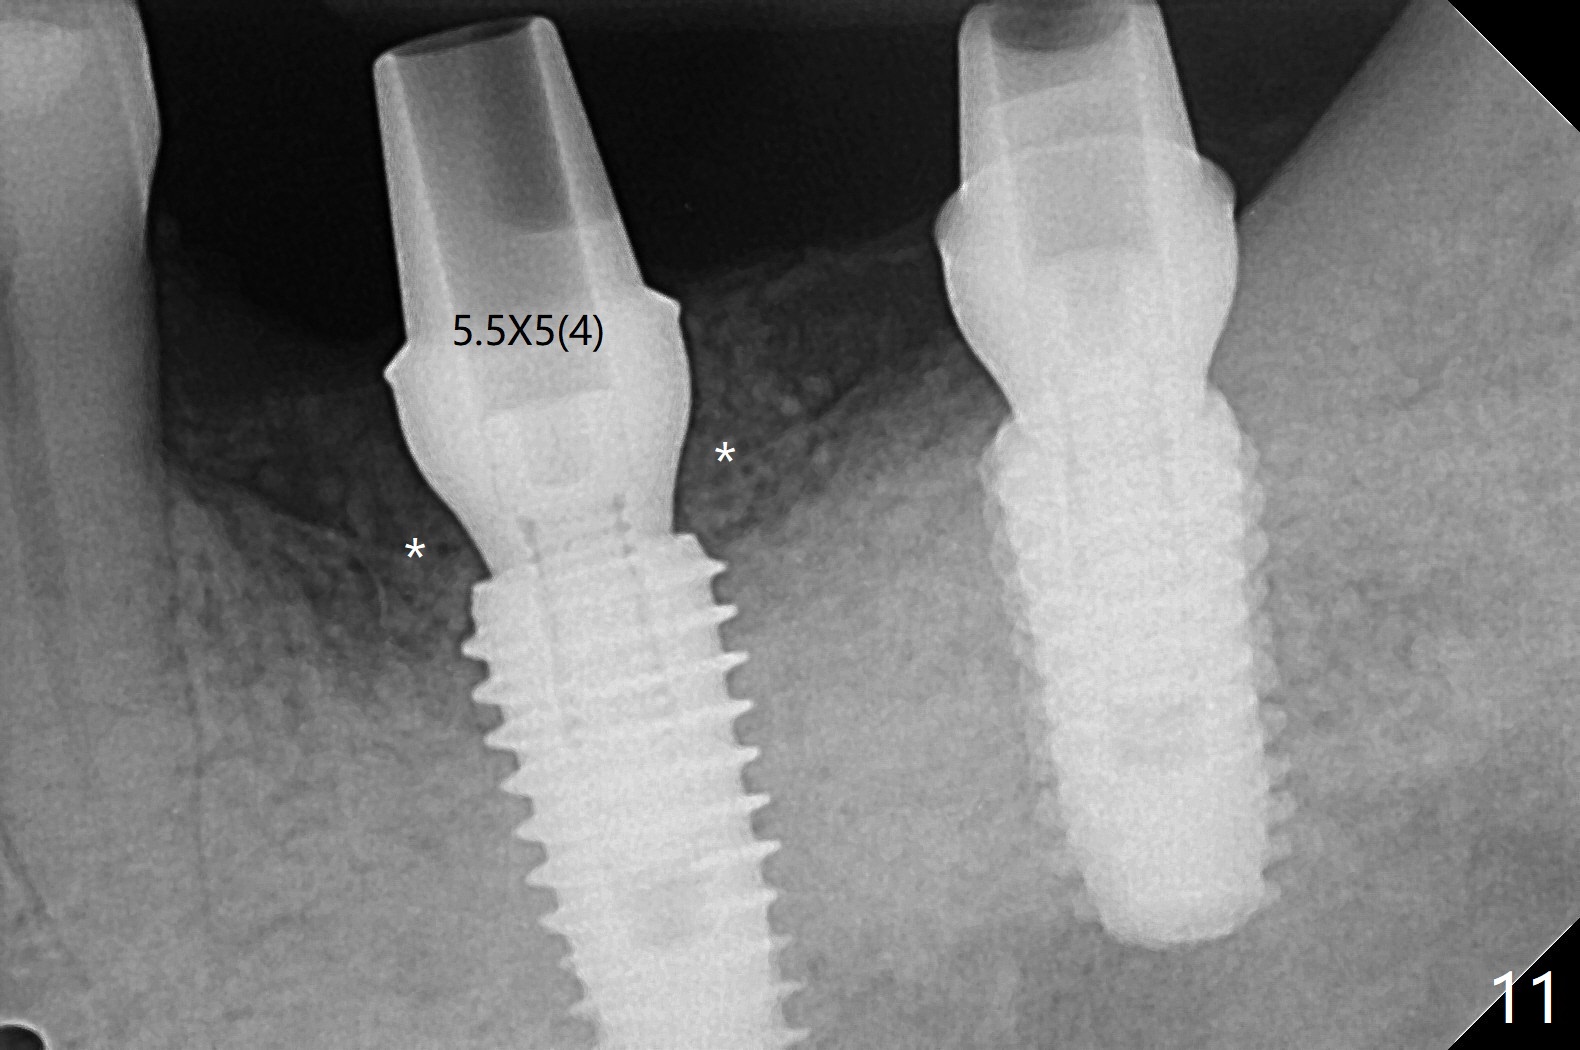

After finishing osteotomy with guide, a 5x14 mm tissue-level implant tap is used without guide because of limited mouth opening. It is not parallel to the implant at #19 (Fig.1). A bone-level implant is barely able to be placed with guide; it is parallel to #19 implant (Fig.2). Pre- and intra-op exam confirms periimplantitis at #19. In addition the horizontally impacted #17 has caries. A large incision is made for #19 debridement and bone graft. #18 bone graft (Fig.2 *) and #17 extraction and Osteogen plug (O) placement. Postop CT shows poor trajectory of #19 implant (Fig.3 (coronal section) free hand placement), which is associated with screw loosening and periimplantitis (lingual (L) threads supracrestal). In contrast #18 implant has good trajectory and placement level (Fig.4). The mesial defect of #19 seems to have been repaired and the implant at #18 osteointegrates 7.5 months postop (Fig.5). The wound at #19 heals except a small slit 7.5 months postop (bone graft, Fig.6). When the incompletely seated healing screw (Fig.2,3) is removed during uncover, it is difficult to place a cemented abutment. A healing abutment is placed instead. In fact the hex of the abutment fractures within the implant well (Fig.7,8 < (due to burial of 1.2 driver inside the abutment and bruxism)). Because of the deeply placed implant, incision is made and surgical long fissure bur is used to section the lingual (Fig.9 L) portion of the hex. When the buccal (B) portion of the hex is being sectioned, the hex dislodges by itself. There is no problem to insert a cemented abutment (Fig.10). Later a longer cuffed abutment is placed and bone graft is placed around the coronal threads (Fig.11 *). The bone graft around #19 implant looks stable 2 weeks post 2nd grafting (Fig.12). Return to Prevent Molar Periimplantitis (Protocols, Table) No Deviation Screw Xin Wei, DDS, PhD, MS 1st edition 02/10/2020, last revision 02/26/2021